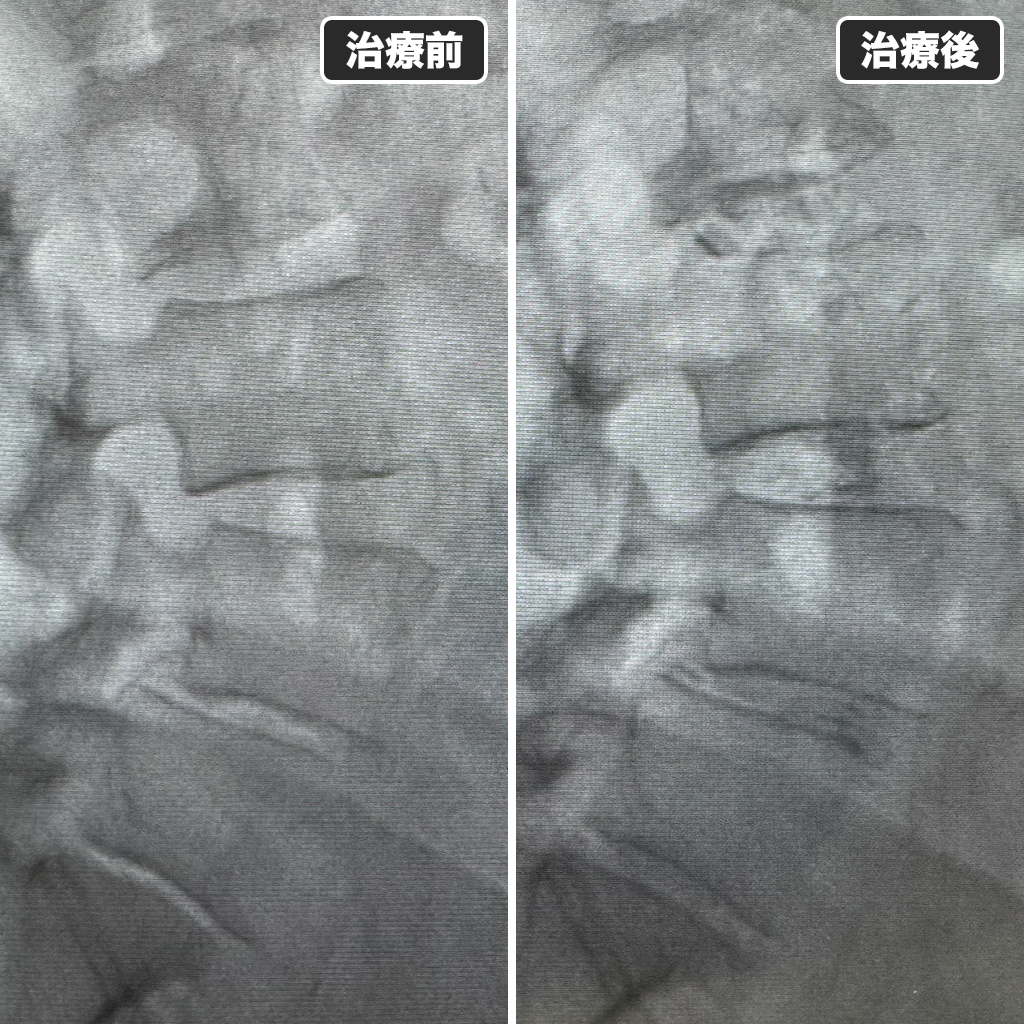

治療前後のレントゲン写真

治療前後のレントゲン写真です。左側が治療前、右側が治療後になります。